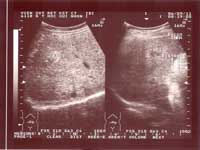

Một số hình ảnh siêu âm tổn thương gan do sán lá gan lớn:

Hình ảnh 7: Khối tổn thương gan do SLGL sau điều trị 3 tháng: Thay đổi chưa đáng kể, một khối tăng âm xen lẫn nhiều micro áp - xe | Hình ảnh 8: Khối tổn thương gan do SLGL sau 3 tháng điều trị bằng Egaten, thay đổi đáng kể:Hai khối tăng âm ít rõ, không rõ giới hạn |